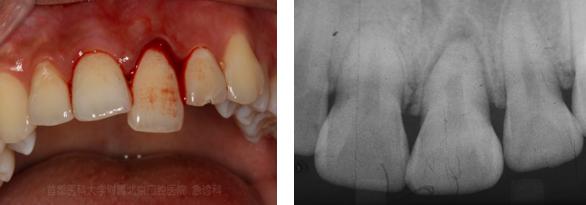

牙周组织外伤,右上中切牙部分脱位,左上中切牙挫入,左上侧切牙